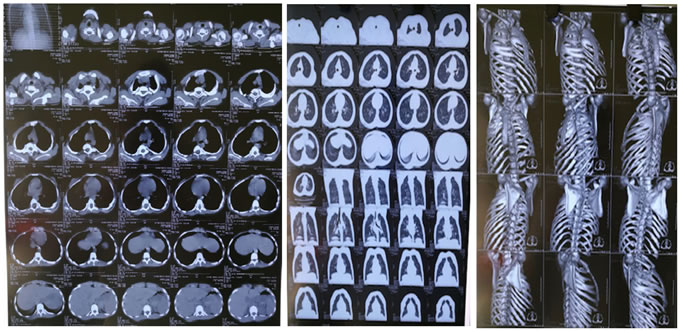

Figure 1                                                        Figure 2                                               Figure 3

There is fusion of left 1st, 2nd, 3rd, and 4rth ribs postetiorly, right 3rd, 4rth, 5th posterior ribs and right 3rd and 4rtg anterior rib with resultant crab like configuration. There is fusion of the posterior elements of D1 to D5 vertebrae with partial /near complete fusion of theor end plates. There is mild degrees of upper sternal protrusion anteriorly with concavity of right lateral border with asymmetrical chest wall. Posterior spina bifida seen at D5 and D6 levels. there is kyphoscoliotic deformity at the upper dorsal spines, concavity towards left. B/L lung fields appears normal and show attenuation pattern. Mediastinum is in midline. No evidence of pericardial/pleural effusion. Cardiothoracic ratio normal.

IMPRESSION: multiple b/l ribs fusion /synostosis with upper thoracic vertebral anomalies and fusion.

S/O: Jarcho Levin syndrome variant ( spondylo-costal variant).